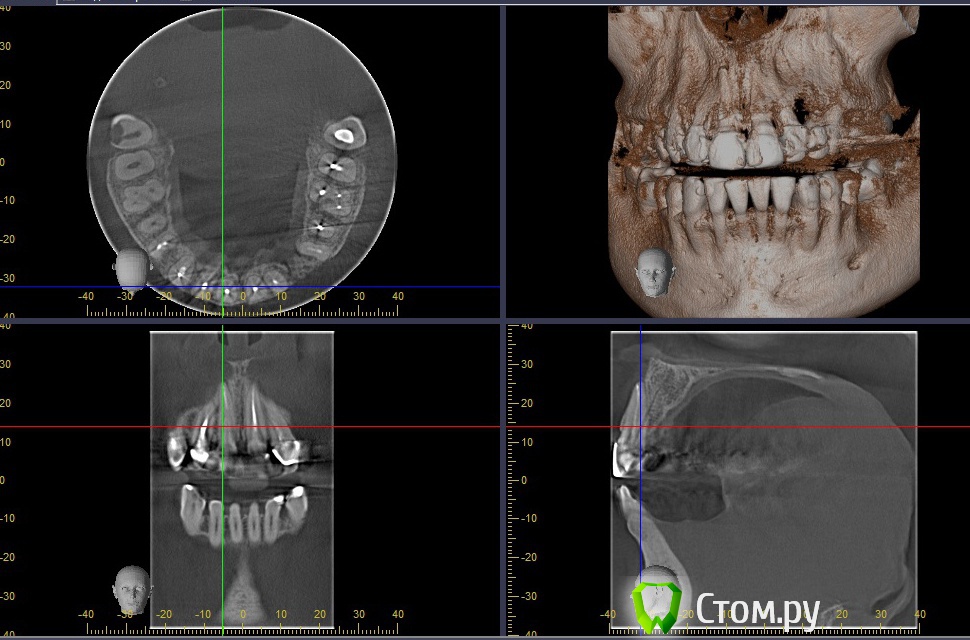

stradalitca Опубликовано 28 мая, 2014 Автор Поделиться Опубликовано 28 мая, 2014 Мужчины, ловите!!!http://s020.radikal.ru/i706/1405/a7/a5d74d5889dd.jpgпотом я немного сдвинула зелёную ось и получилось такhttp://s003.radikal.ru/i202/1405/bd/6606841bbdda.jpgа потом я ещё сдвинула зелёную ось и получилось вот такhttp://s020.radikal.ru/i723/1405/c8/8fe516c63abf.jpgа это зубик 22 в другой проекции( он просто похоже изогнутый, потому и кажется, что пломбровка в сторону идёт)http://s020.radikal.ru/i723/1405/e8/1fe0ffa721ab.jpgну и полная "красота" моего рта))))) мне кажется там ещё под коронками сверху 6, и 7 кариес вовсю идёт. Врач мне посему-то пломбировать не стал, я правда добилась, чтоб он хоть высверлил разъеденную часть. Вообщем он мне по сути цементом коронку залил и прицепил( вместо пломбы оказался цемент)ещё я пришла к выводу, что мне надо ставить пломбы на нижних - 7 справа и 4 слева.http://s43.radikal.ru/i101/1405/3b/411890da6471.jpgчто скажете? Ссылка на комментарий

Korel Опубликовано 29 мая, 2014 Поделиться Опубликовано 29 мая, 2014 Помню, что именно в правый зуб в конце, по ощущениям, врач что-то вонзила в канал, что я вздрогнула - как будто аж насквозь зуб и дальше. В тотже день появилась небольшая тупая боль при нажатии в районе верхушки корня( около правой ноздри). Похоже на перфорацию отмеч. зелён. стрелочкой. d7e4ef25a75e.jpg очень похоже на перфорацию нет, думаю, что это не перфорация, а просто с той проекции видно уже другой зуб как же мне нравится ваш попугай!!! Это попугаиха!!!! Ссылка на комментарий

stradalitca Опубликовано 29 мая, 2014 Автор Поделиться Опубликовано 29 мая, 2014 я никого не хотела обидеть. И тем более Мону.насчёт проткнуть . было так. Она вроде пролечила канал, в конце как будто что-то засунула( ну не знаю, может чтоб поплотнее утрамбовать_ так, что мне показалось, что снизу и до апекса и за апекс ширнуло. Далее она зажигалкой прогрела инструмент и прижгла выход ( или вход?)канала и стала световую пломбу ставить.вот. так всё и было. Вы уже видели новые проекции? по-моему это просто двойка на горизонте проглядывала. Ссылка на комментарий

Korel Опубликовано 1 июня, 2014 Поделиться Опубликовано 1 июня, 2014 Уважаемые стоматологи, кто-нибудь смотрел последние мои снимки? ( те, где вроде как двойка проглядывает, а не перфорация)? Склоняюсь к перфо. в начале темы я раместила три фото. на одном, в коричневых тонах, этот зуб( 11) на корне какой-то не такой. в смысле верхушке зуба. Пожалуй, меня это единственное, что смущает. Аналогично. я никого не хотела обидеть. И тем более Мону. Мона не обидчивая)) Ссылка на комментарий